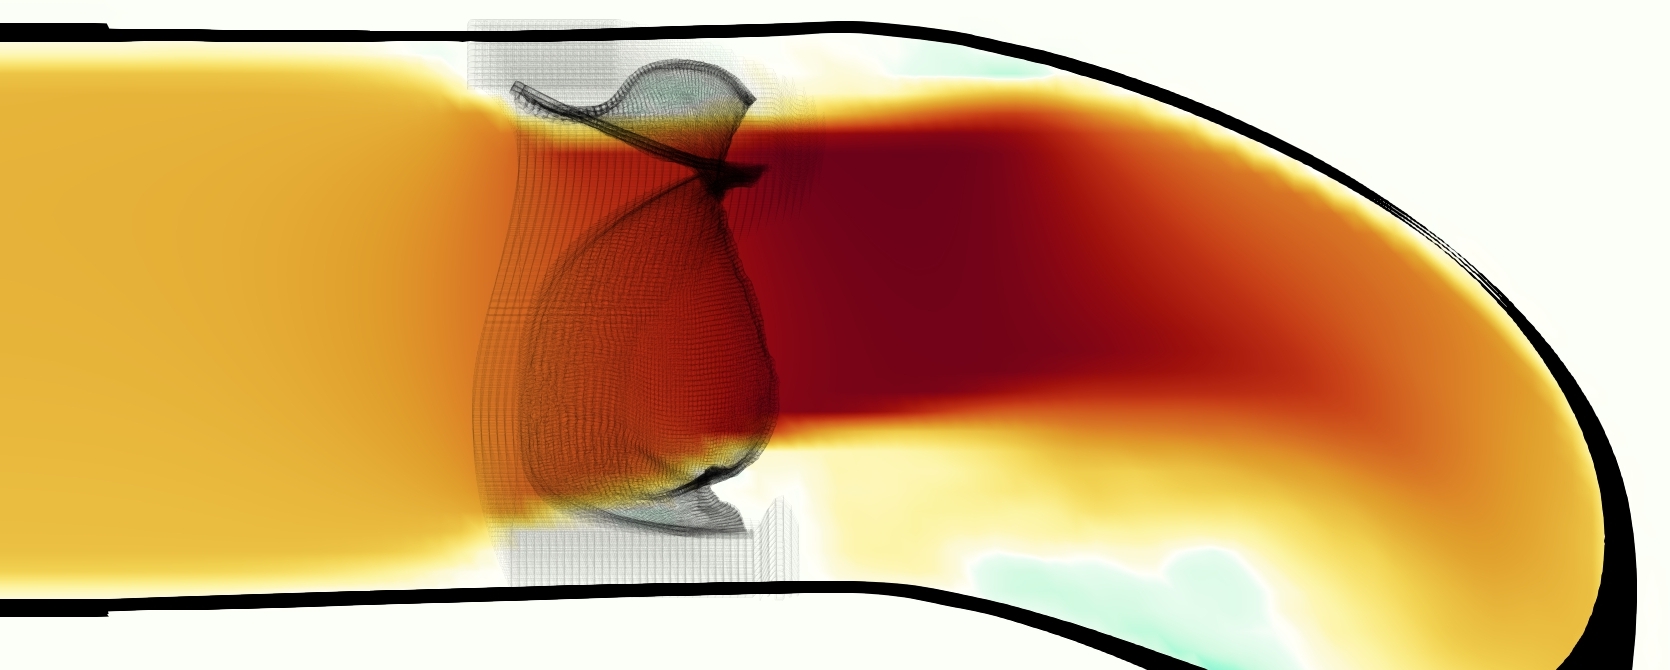

The emergent hemodynamics showed excellent qualitative agreement with experiments. Slice views of the axial component of fluid velocity ( component) in the sagittal plane that cuts through the center of the vessel, parallel to the flow direction, are shown in Figure 5. The flow in both the simulation and the experiment began to accelerate at the same time, with a jet forming through the open valve leaflets. The velocity, angle, and shape of the jet agreed well between the two cases during systole. The simulation captured the slight upward angle of the jet, which was not fully centered in the vessel. It also matched the location where the jet impacts the wall and the slower speed of the jet as it turns with the MPA downstream. As the flow decelerated, the fluid along the interior curve of the vessel reversed first while forward flow persisted where the jet was strongest, as seen in both the simulation and experimental results.

In both the experiment and the simulation, a separation region of reverse flow developed along the interior curve of the vessel under the core jet through the valve. The reverse flow began to develop at the same time in the cardiac cycle and grows throughout systole. The simulation lacked reversed flow in the entire region where reversed flow was present in the experiment, but this region developed some flow separation and had much slower flow than elsewhere in the vessel. Thus, the simulation captured that this is a distinct region from the core jet through the valve opening. There was a smaller amount of slower and slightly reversed flow along the outer curve of the vessel, close to the valve annulus and scaffold support. This region was well-matched between the experiment and the simulation.

A comparison between the phase-averaged velocity resampled onto the MRI grid, the phase-averaged velocity without resampling, the instantaneous flow field without resampling and the MRI velocity field is shown in Figure 8. The coarser resolution is visible as a “stair-stepping” or “pixelated” effect on the phase-averaged resampled velocity, whereas the edges of the jet are more smooth in the phase-averaged velocity with no resampling. Otherwise, the resampled velocity appears qualitatively similar to the phase-averaged velocity with no resampling. Fine scale features were present in the instantaneous field that were lost in the phase-averaging and resampling process. There was more variation in the local velocity of the center of the jet and local areas of high velocity at the edges of the jet that suggested vortices. Vortical structures adjacent to the jet and in the areas of reversed flow were apparent. These comparisons suggest that 4D flow MRI data may lose substantial fine-scale flow features in the flow field via phase-averaging.